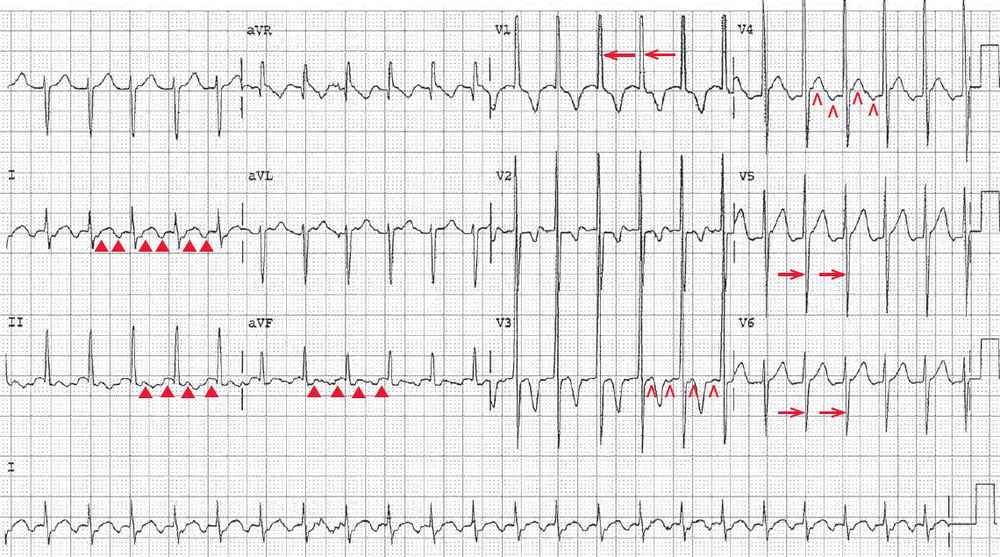

The ECG shows there is a regular rhythm with a rate of 280 bpm. There are no P waves seen before or after any of the QRS complexes. The QRS complex duration is prolonged (0.12 sec), and there is a rightward axis between +90° and +180° (QRS negative in lead I and positive in lead aVF).

The QRS complex morphology is unusual with a tall R wave in lead V1 (←), but a small R wave and deep S waves in leads V5–V6 (→). While the morphology resembles a right bundle branch block (RBBB), it is not typical. Hence this is a wide QRS complex tachycardia.

There is no obvious atrial activity. The two potential rhythms are atrial flutter with 1:1 conduction or ventricular tachycardia, which at this rate is often referred to as ventricular flutter.

The fact that the patient has known congenital heart disease does not help establish a diagnosis. However, there are beat-to-beat changes in QRS amplitude (↓, ↑). This is termed electrical or QRS alternans. There are also beat-to-beat changes in the T waves (▲, ▼) that are T-wave alternans.

The presence of electrical (or QRS) and T-wave alternans is more suggestive that this is a supraventricular tachyarrhythmia, and likely flutter with 1:1 AV conduction. Although it has been reported that electrical alternans may occur in ventricular tachycardia, this is very unusual. It may be more frequently seen in a right ventricular outflow tachycardia or a fascicular tachycardia, which is a type of ventricular tachycardia in which one of the fascicles (most often the left posterior fascicle) is part of the circuit of the tachycardia.

The QRS complex morphology is not typical for a right ventricular outflow tachycardia (which has a left bundle branch block morphology and a normal axis). Fascicular tachycardias are not usually this rapid, although the right axis and RBBB morphology does suggest a possible left anterior fascicular tachycardia, which is far less common. Therefore, the most likely diagnosis is atrial flutter, with an unusual QRS complex morphology as the result of underlying congenital heart disease. The morphology is suggestive of right ventricular hypertrophy.